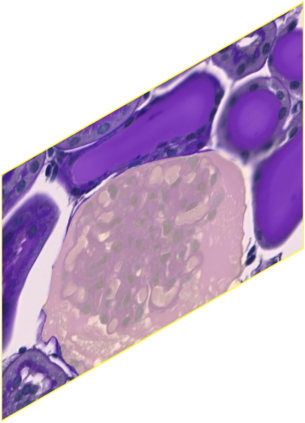

In digital pathology, the traditional method for deep learning-based image segmentation typically involves a two-stage process: initially segmenting high-resolution whole slide images (WSI) into smaller patches (e.g., 256x256, 512x512, 1024x1024) and subsequently reconstructing them to their original scale. This method often struggles to capture the complex details and vast scope of WSIs. In this paper, we propose the holistic histopathology (HoloHisto) segmentation method to achieve end-to-end segmentation on gigapixel WSIs, whose maximum resolution is above 80,000$\times$70,000 pixels. HoloHisto fundamentally shifts the paradigm of WSI segmentation to an end-to-end learning fashion with 1) a large (4K) resolution base patch for elevated visual information inclusion and efficient processing, and 2) a novel sequential tokenization mechanism to properly model the contextual relationships and efficiently model the rich information from the 4K input. To our best knowledge, HoloHisto presents the first holistic approach for gigapixel resolution WSI segmentation, supporting direct I/O of complete WSI and their corresponding gigapixel masks. Under the HoloHisto platform, we unveil a random 4K sampler that transcends ultra-high resolution, delivering 31 and 10 times more pixels than standard 2D and 3D patches, respectively, for advancing computational capabilities. To facilitate efficient 4K resolution dense prediction, we leverage sequential tokenization, utilizing a pre-trained image tokenizer to group image features into a discrete token grid. To assess the performance, our team curated a new kidney pathology image segmentation (KPIs) dataset with WSI-level glomeruli segmentation from whole mouse kidneys. From the results, HoloHisto-4K delivers remarkable performance gains over previous state-of-the-art models.